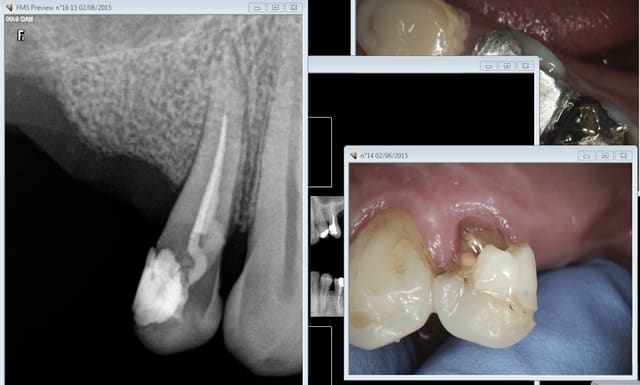

Mouahaha à l'instant patient qu'un confrère n'a pas eu le temps de prendre en urgence. -))))

C'est joli hein tous ces compos et amalgames de merde sur dents dévitalisées selon les données acquises de la science, hein ?-))))))

Alors rte ou pas rte, inlay core ou pas inlay core ? -))))